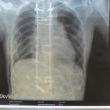

Ismay scoliose

Scoliose-info

Syringomelie